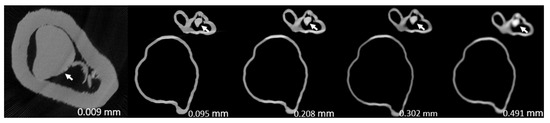

- Model 1: >90% and <50% stenosis in left main stem (LM) and left anterior descending (LAD) coronary artery, respectively.

- Model 2: >90% and 70% stenosis in LAD and left circumflex (LCx), respectively.

- Model 3: >90% and 70% stenosis in proximal LCx and middle LCx, respectively.